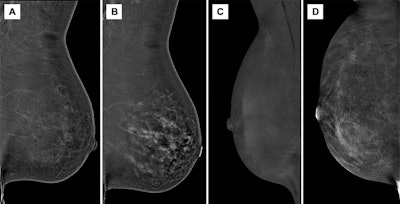

Images depict ongitudinal background parenchymal enhancement (BPE) changes at contrast-enhanced mammography (CEM) related to tamoxifen therapy and cessation. Recombined (A, B) left and (C, D) right mediolateral oblique CEM images in two different 51-year-old female patients who underwent imaging while receiving tamoxifen therapy (A, C) and after cessation of therapy (B, D) show minimal BPE during tamoxifen therapy, which increased to marked and moderate BPE grades, respectively, after cessation.Images and caption courtesy of the RSNA.

Images depict ongitudinal background parenchymal enhancement (BPE) changes at contrast-enhanced mammography (CEM) related to tamoxifen therapy and cessation. Recombined (A, B) left and (C, D) right mediolateral oblique CEM images in two different 51-year-old female patients who underwent imaging while receiving tamoxifen therapy (A, C) and after cessation of therapy (B, D) show minimal BPE during tamoxifen therapy, which increased to marked and moderate BPE grades, respectively, after cessation.Images and caption courtesy of the RSNA.